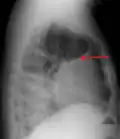

A pleural effusion as seen on lateral upright chest x-ray -

Pleural effusion as seen behind the heart.[20]